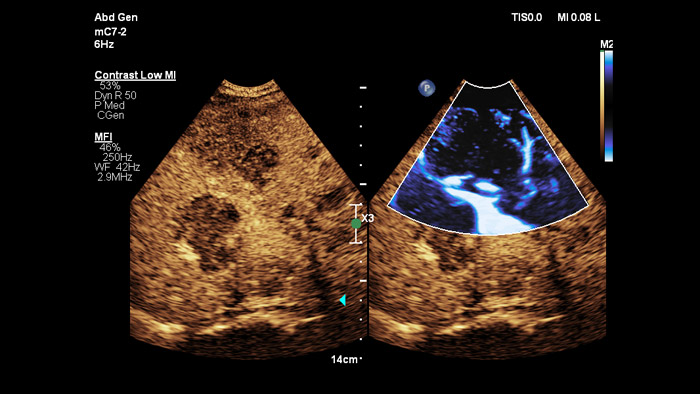

Ultraschall-Kontrastmittel können die Rolle des Ultraschalls verändern: Verstärkungsmuster von Leberläsionen können von Klinikteams in Echtzeit untersucht werden. Bei Ultraschallgeräten von Philips sind kontrastmittelverstärkte Ultraschalluntersuchungen nahtlos in den Standardablauf integriert.

Jeder Mensch ist anders. Die PureWave Kristalltechnologie bietet ein verbessertes Eindringvermögen bei schwer schallbaren Patienten ohne Abstriche bei der Detailauflösung, der Doppler-Empfindlichkeit und dem kontrastmittelverstärkten Ultraschall (CEUS).